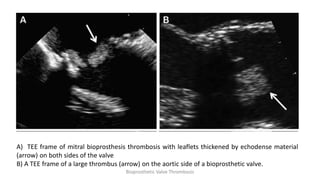

Echocardiographic features

• Direct visualization of valve thrombosis in rare cases

• 50% mean gradient increase compared with the initial post-operative evaluation

• Increased cusp thickness (>2 mm), especially on the downstream aspect of the

BPV (ventricular side for mitral and tricuspid prostheses, arterial side for aortic and

pulmonary prostheses)

• Abnormal/reduced leaflet mobility

• Regression of BPV abnormalities with OAC, usually within 1–3 months of OAC

initiation

A) TEE frame of mitral bioprosthesis thrombosis with leaflets thickened by echodense material

(arrow) on both sides of the valve

B) A TEE frame of a large thrombus (arrow) on the aortic side of a bioprosthetic valve.